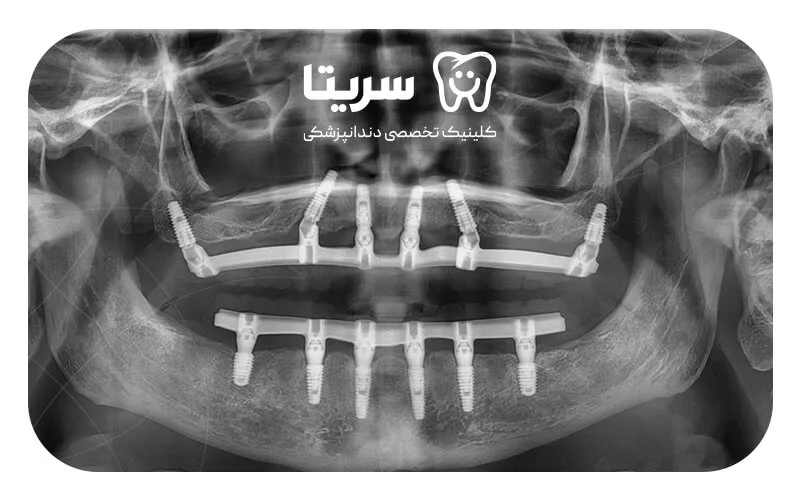

۱. تصویربرداری و معاینه

در مرحله اول، پزشک ابتدا باید با در اختیار داشتن عکسهای (OPG) و (CBCT) به بررسی وضعیت سلامت استخوان فک بپردازد. هدف از این معاینه این است که بر اساس تصویرهای رادیوگرافی، ایمپلنت مناسب با ساختار فک بیمار ساخته شود.

۲. اسکن دیجیتال گرفتن و قالبگیری از فک

در این مرحله، لازم است برای درست قرار گرفتن قالب فلزی ایمپلنت ساب پریوستئال در جای مناسب، اسکن دیجیتال یا همان سه بعدی از استخوان فک گرفته شود. این مرحله برای سفارشیسازی ایمپلنت، بسیار مرحله مهمی است.